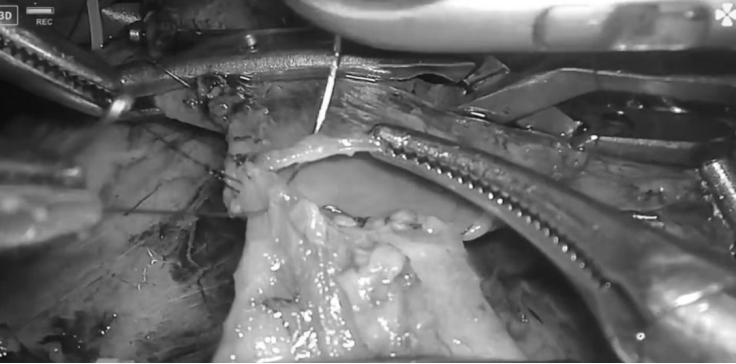

面对复杂的手术区域,郑志鹏主任带领团队迎难而上,依托丰富的腹腔镜外科技术,历时7小时完成手术。术中通过5个小孔,精细解剖肝动脉、门静脉、肠系膜上静脉等多条重要血管,完整切除肿瘤及受侵犯的门静脉,仔细将门静脉缝合,严密对合后的血管通畅无渗血。患者术后第5天恢复饮食,10天后顺利出院,住院时间比传统开腹手术缩短近一半时间,更关键的是,腹部仅留5个0.5-25px小孔,肚子上没有“蜈蚣疤”。

郑志鹏主任介绍:胰十二指肠切除术(LPD)本身已是普外科公认的“珠穆朗玛峰级”手术,需切除胰头、十二指肠、胆总管、胆囊及部分胃这五个器官,并完成胰肠、胆肠、胃肠三重吻合。而此次手术的难点在于联合门静脉切除重建,需在腹腔镜下精准分离被肿瘤侵犯的血管,切除受累血管后逐层精准吻合血管壁,将血管两端完美对合,血管吻合要求“毫米级精度”,确保血流通畅且无渗漏,稍有不慎便可能导致大出血或术后血栓形成,对缝合精度要求极高。相比传统开腹手术,腹腔镜技术的优势在于放大10倍视野,配合精细器械实现“血管绣花”,创伤更小且精度更高,疼痛轻,患者心理负担显著降低,且术后疤痕隐蔽,兼顾疗效与美观。